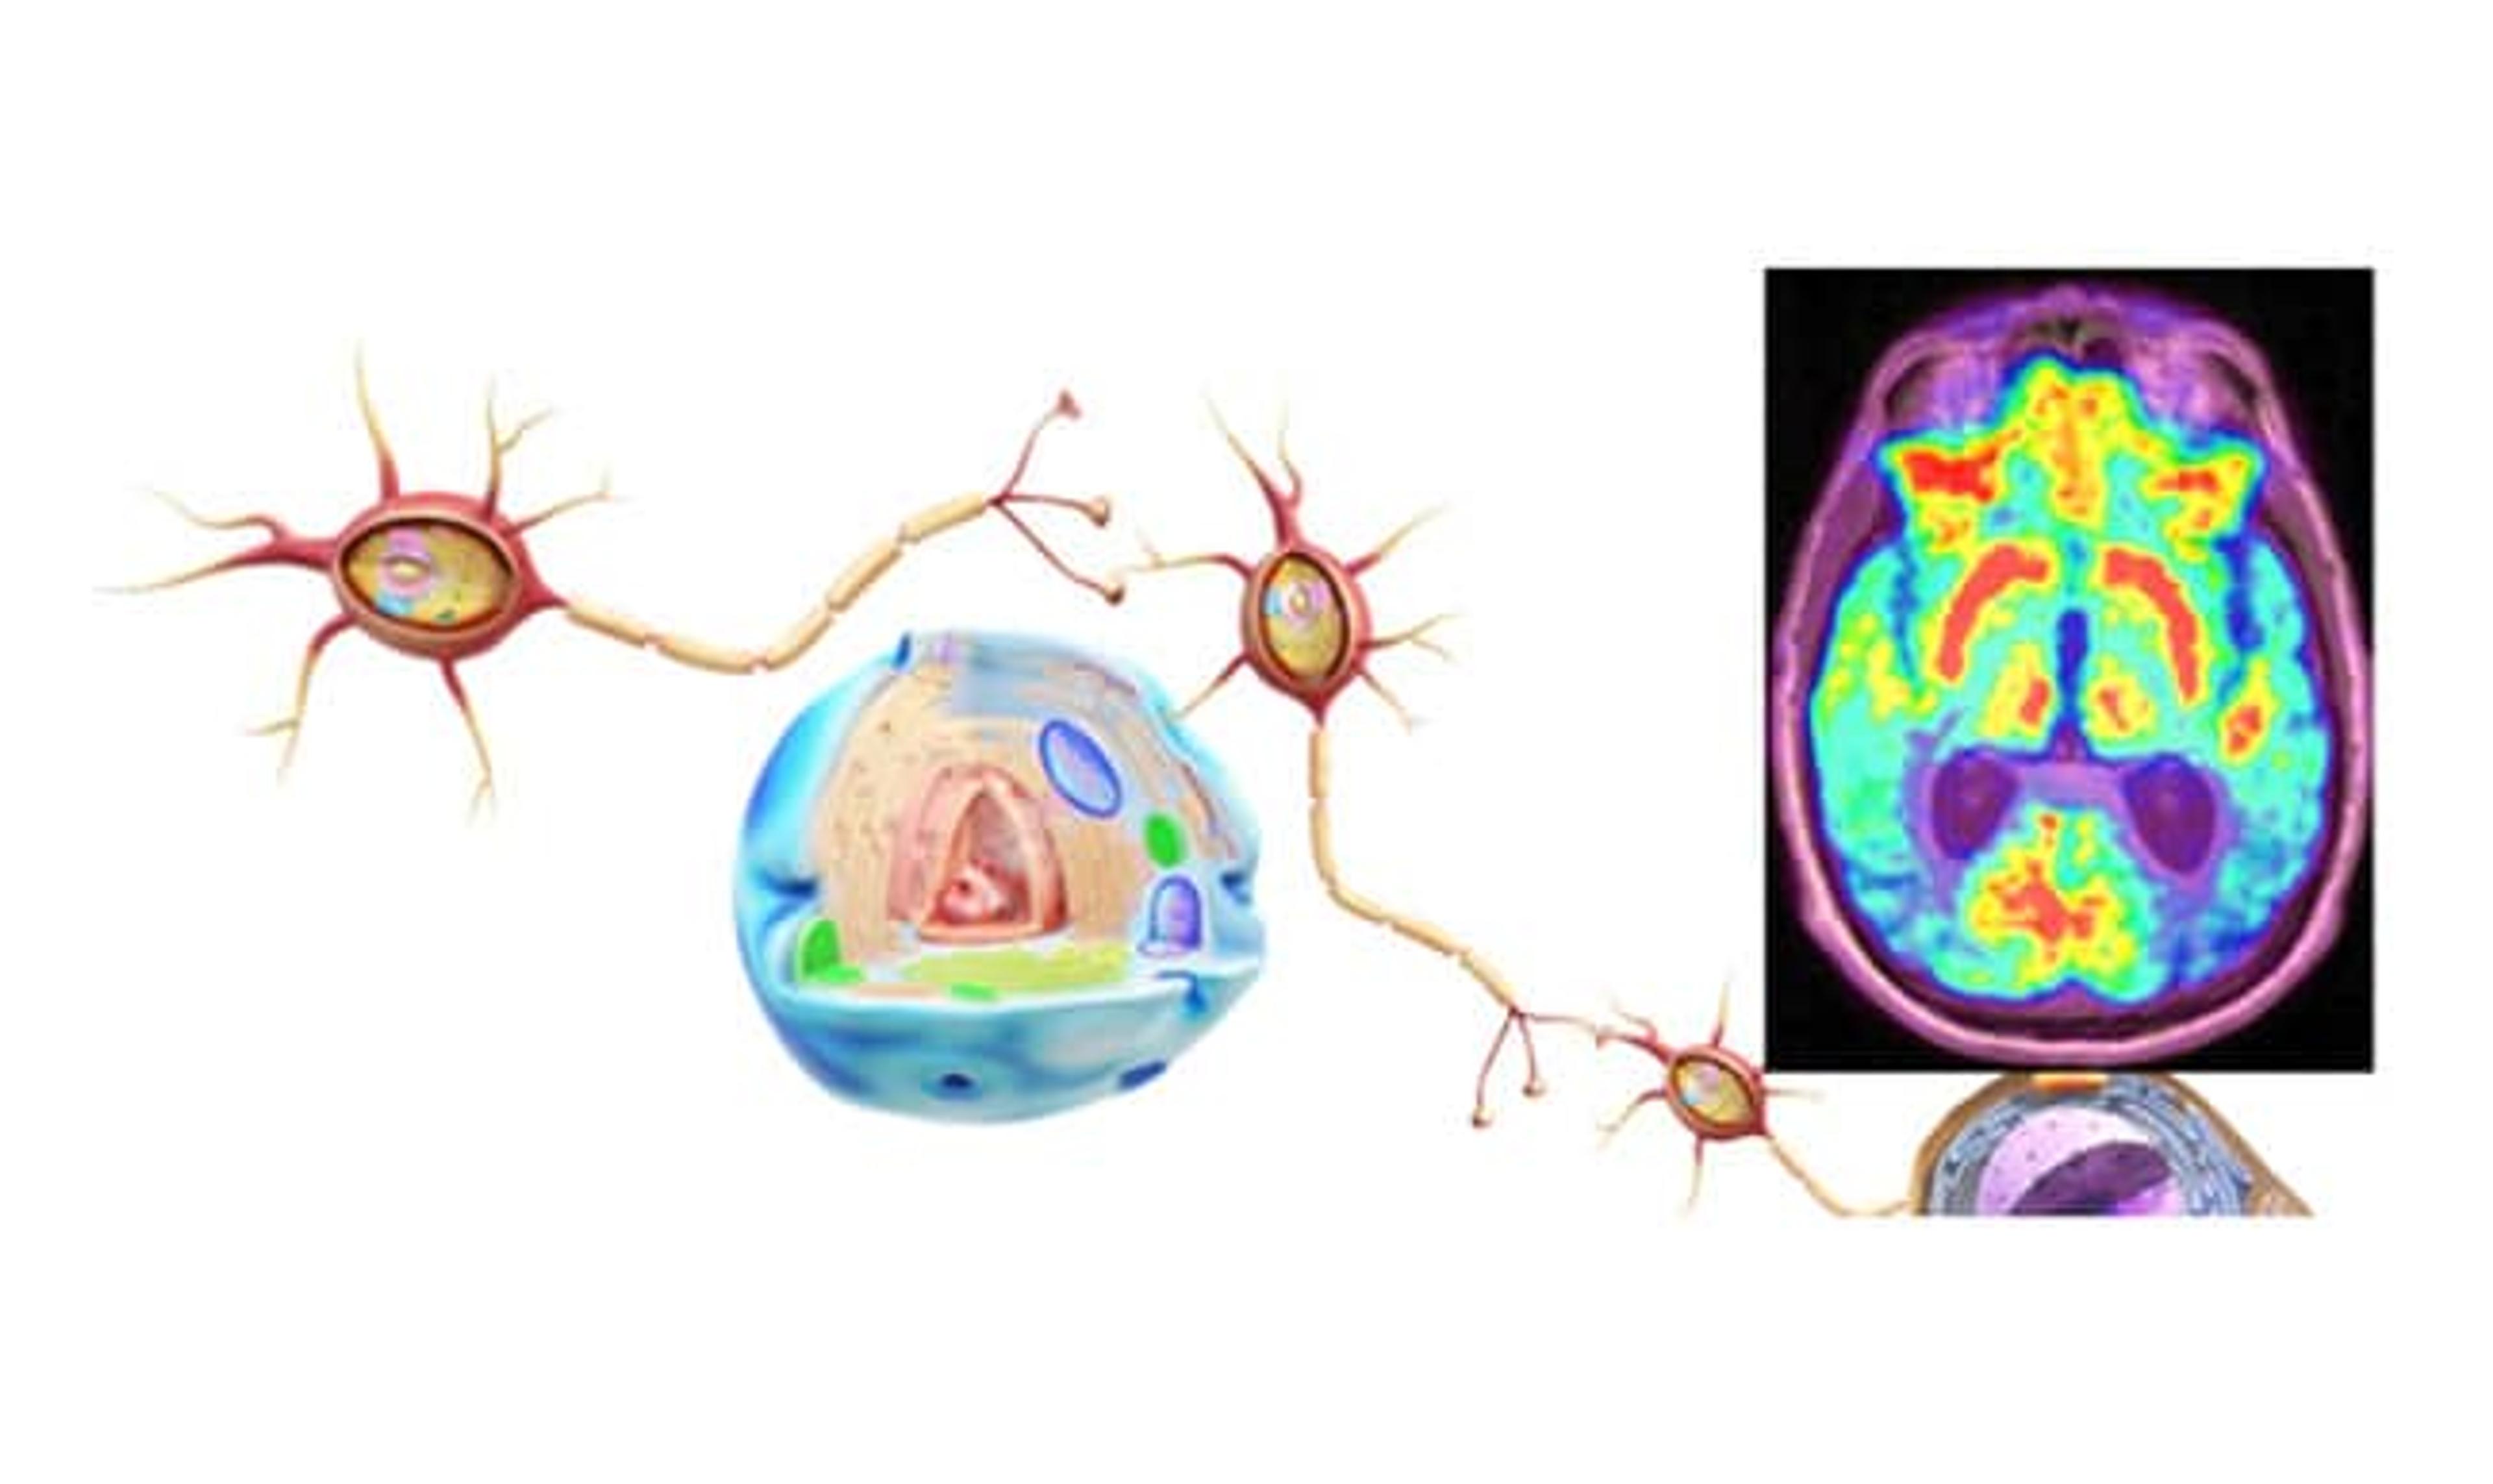

Understand how PRISM Imaging can assist in identifying and monitoring neurodegenerative and neurocognitive disorders.

In the domain of neurodegenerative and neurocognitive disorders, PRISM Imaging extensively investigates conditions including but not limited to:

Through cutting-edge imaging technology, PRISM aims to illuminate the path to better understanding and treatment for these challenging conditions.